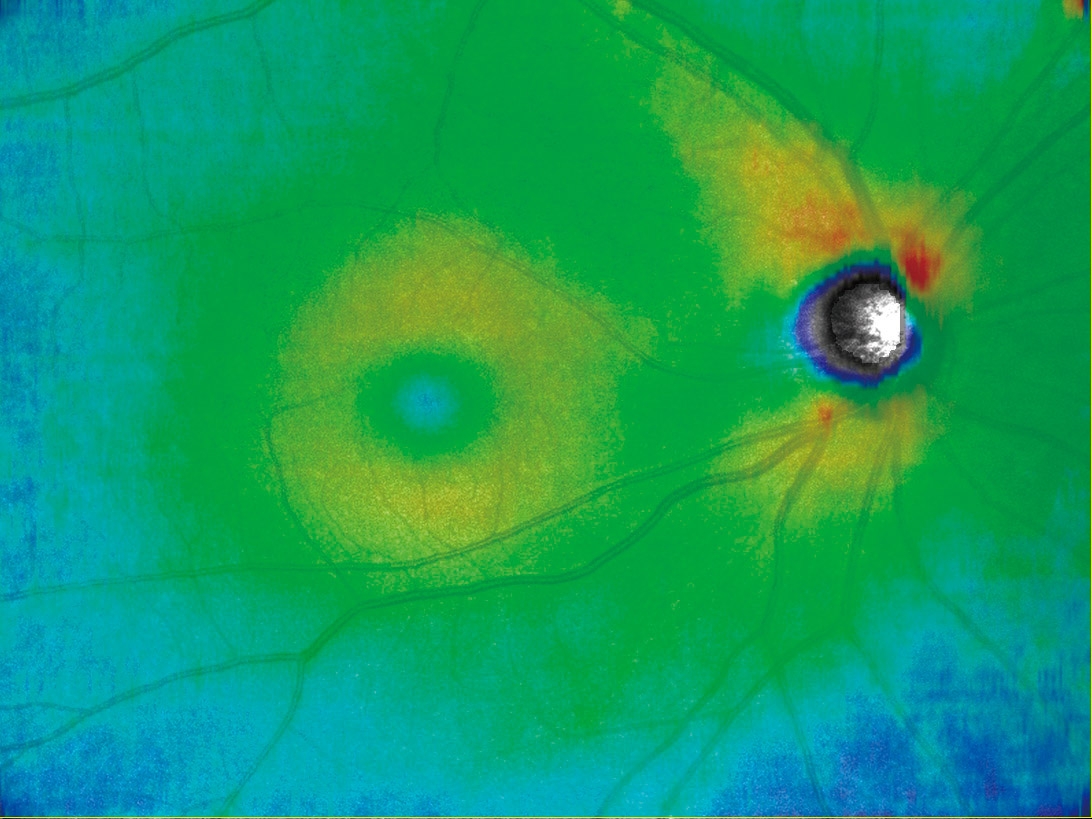

任意設定により5種類(初期設定:網膜全層、表層、深層、外層、脈絡膜)のパノラマが同時に自動合成できます。

網膜全層 HD4 4.5×4.5mm 6枚 パノラマ |

網膜表層 |

網膜深層 |

網膜外層 |

脈絡膜 |